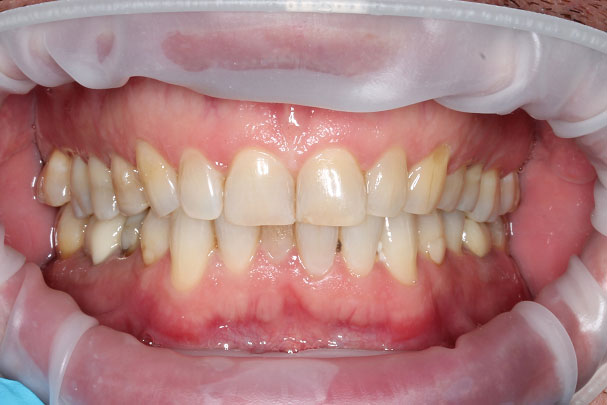

Улыбка счастливого пациента до и после лечения в клинике АГАМИ - на фото.

Пациенту было проведено протезирование зубов на имплантатах, протезирование на собственных зубах и установка виниров на передние зубы. Пациент остался очень доволен полученным результатом, улыбка изменилась до неузнаваемости.

Пациент остался очень доволен полученным результатом, улыбка изменилась до неузнаваемости.